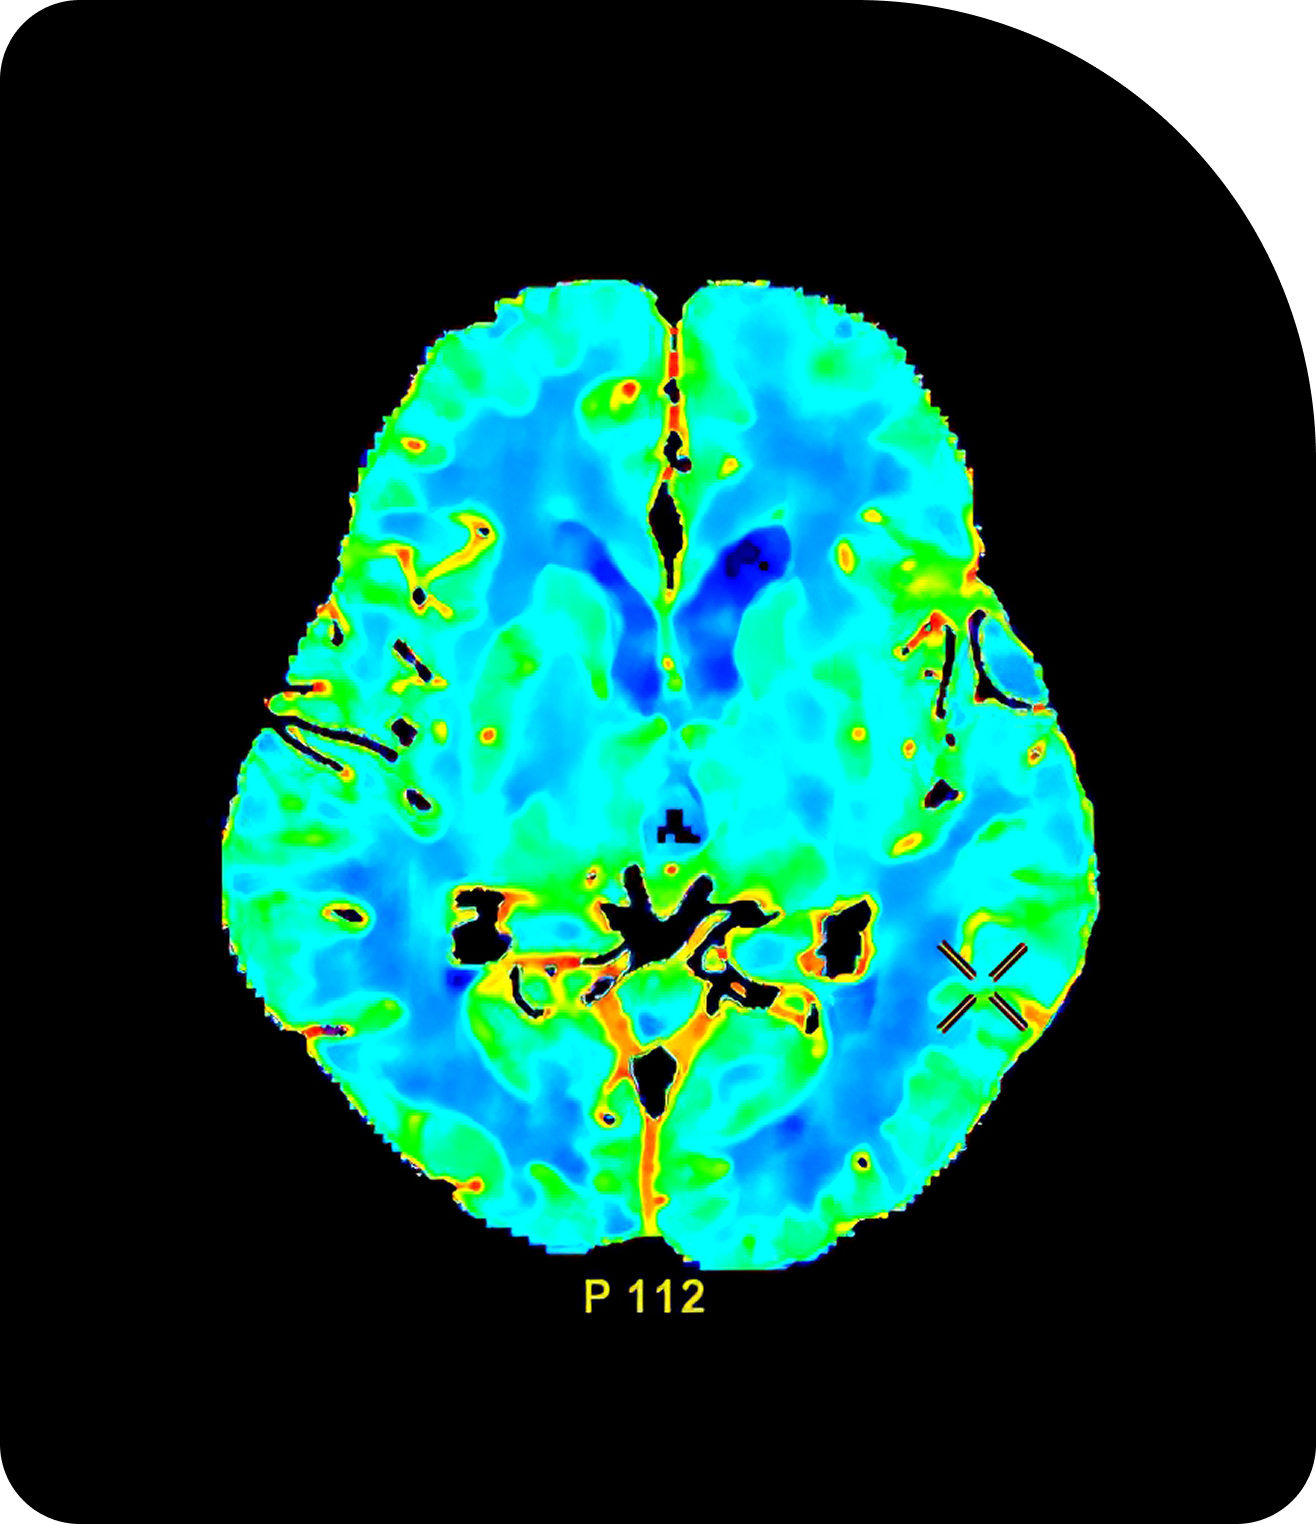

Compare Imaging TechnologiesAdaptive Radiotherapy in Action

Key clinical trials highlight Adaptive Radiotherapy’s feasibility, safety, and efficacy across tumor sites.

The evidence base to date underscores Adaptive Radiotherapy’s transformative potential in multiple disease sites. Across gynecologic, brain, prostate, liver, and head & neck cancers, Adaptive Radiotherapy consistently enables personalized treatment, improved local control, and reduced toxicity.